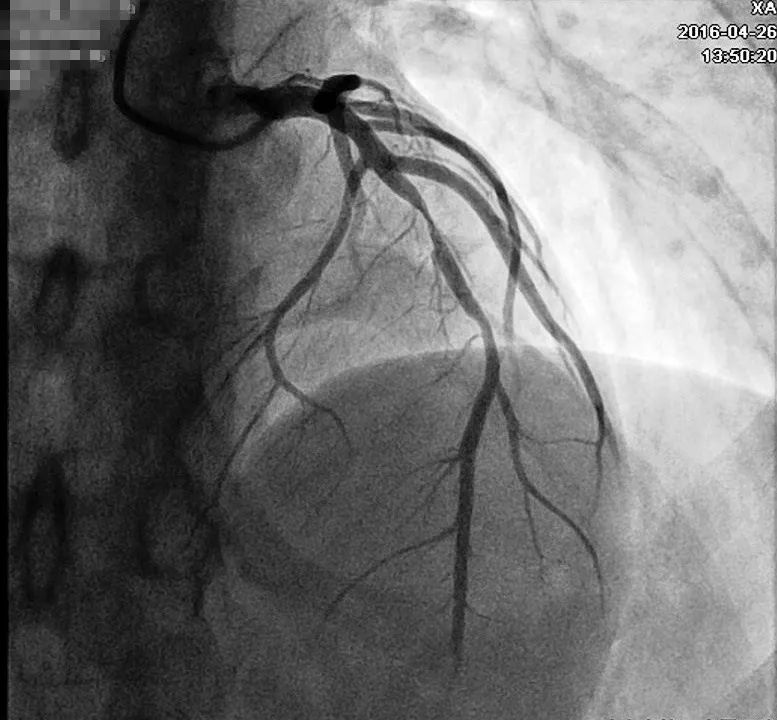

回顾患者病例特点:青年男性,有典型心绞痛发作病史,心电图有特征性改变及演变(胸痛发作时心电图正常;胸痛缓解时,V2~V5导联T波倒置),考虑Wellens综合征。行冠状动脉造影检查示左前降支(LAD)近中段80%~90%弥漫性狭窄,血流慢(图6),右冠近段狭窄20%~30%,回旋支开口狭窄20%~30%(图7)。于LAD置入2枚支架,复查造影提示支架置入处无残余狭窄(图8)。术后规律服用上述药物治疗,未再发作心绞痛。

图6